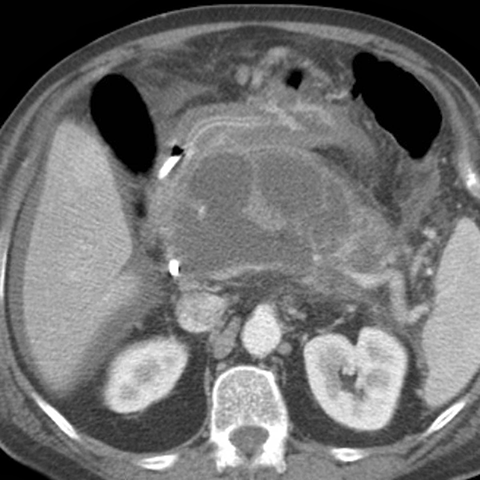

Pancreatic Pseudocyst [3 of 3]